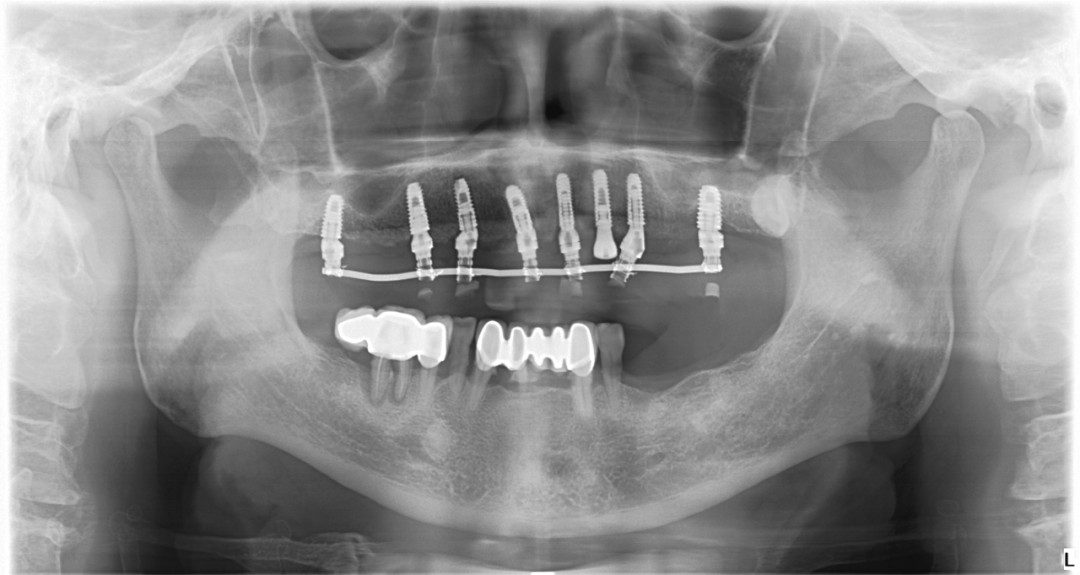

1、基本資料

•  基本資料:趙先生,男, 69歲,體??;上頜多顆牙缺失,牙位13、1211、21留有殘根,長期佩戴傳統(tǒng)活動假牙,大聲說話時活動假牙易脫落,且咀嚼效率低下;下頜常規(guī)固定修復(fù),牙位35、36、37缺失。

• 主訴:上頜傳統(tǒng)活動假牙固位不好,要求種植修復(fù)。

• 治療方案:經(jīng)過充分溝通確定,上頜采用數(shù)字化種植導(dǎo)板輔助植入,拔除剩余殘根,即拔即種+即刻修復(fù);下頜缺失牙位擇期常規(guī)種植修復(fù)。

【術(shù)前照片】

2、導(dǎo)板設(shè)計方案

本次設(shè)計方案是以初次CBCT結(jié)果為患者制定初步的治療方案,取印模并制作石膏模型,根據(jù)治療方案制作放射性導(dǎo)板(帶有放射性標(biāo)志點),讓患者佩戴放射性導(dǎo)板(帶有放射性標(biāo)志點)拍攝二次CBCT,同時將臨時修復(fù)體全貌進(jìn)行單獨掃描,將二次CBCT和修復(fù)體掃描影像整合。在整合影像中進(jìn)行三維重建,結(jié)合修復(fù)體和骨組織的信息,制定最佳的種植方案,包括確定種植體的位置、數(shù)量、角度、深度等,最后生成導(dǎo)板設(shè)計方案。

4術(shù)后照片

本次案例應(yīng)用數(shù)字化種植導(dǎo)板輔助定位植入,手術(shù)過程非常順利,即拔即種在時間上也有很大的優(yōu)勢,拔除壞牙同時植入人工牙根,可以節(jié)省就診時間,縮短種植牙療程,減少痛苦,讓患者手術(shù)當(dāng)天就能重新?lián)碛腥笔У难例X,恢復(fù)了部分咬合功能和美學(xué)效果,受到了患者的夸贊與好評!